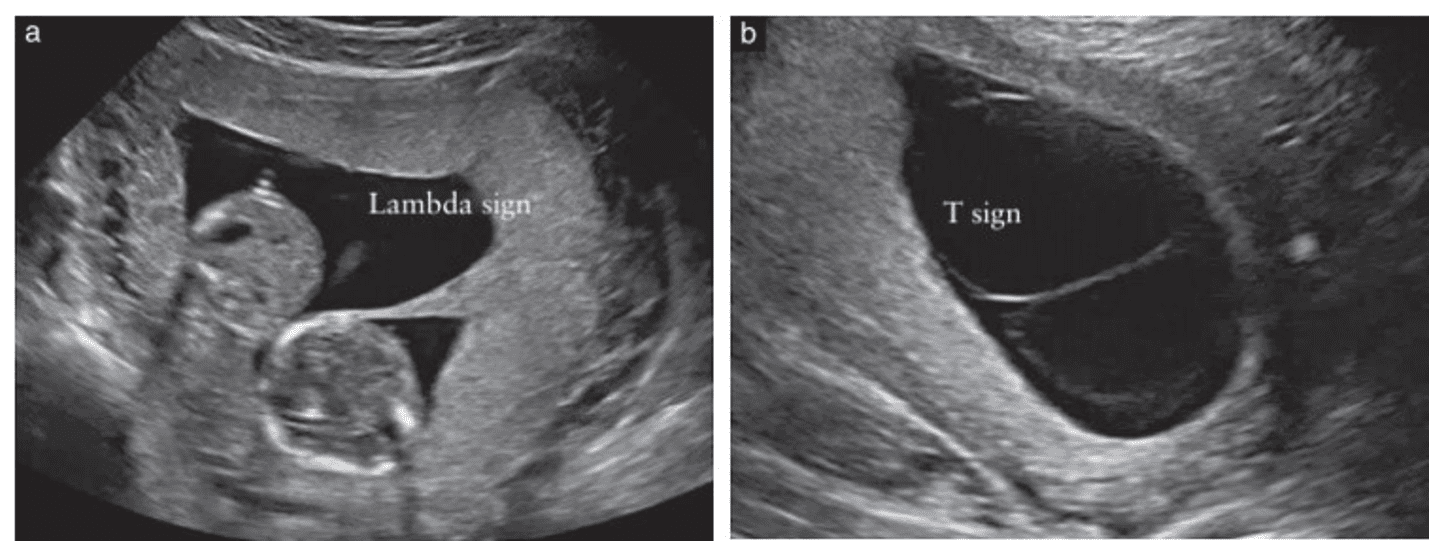

Hướng Dẫn Thực Hanh Isuog Vai Tro Của Sieu Am Trong Song Thai Thư Viện Y Học Lam Sang